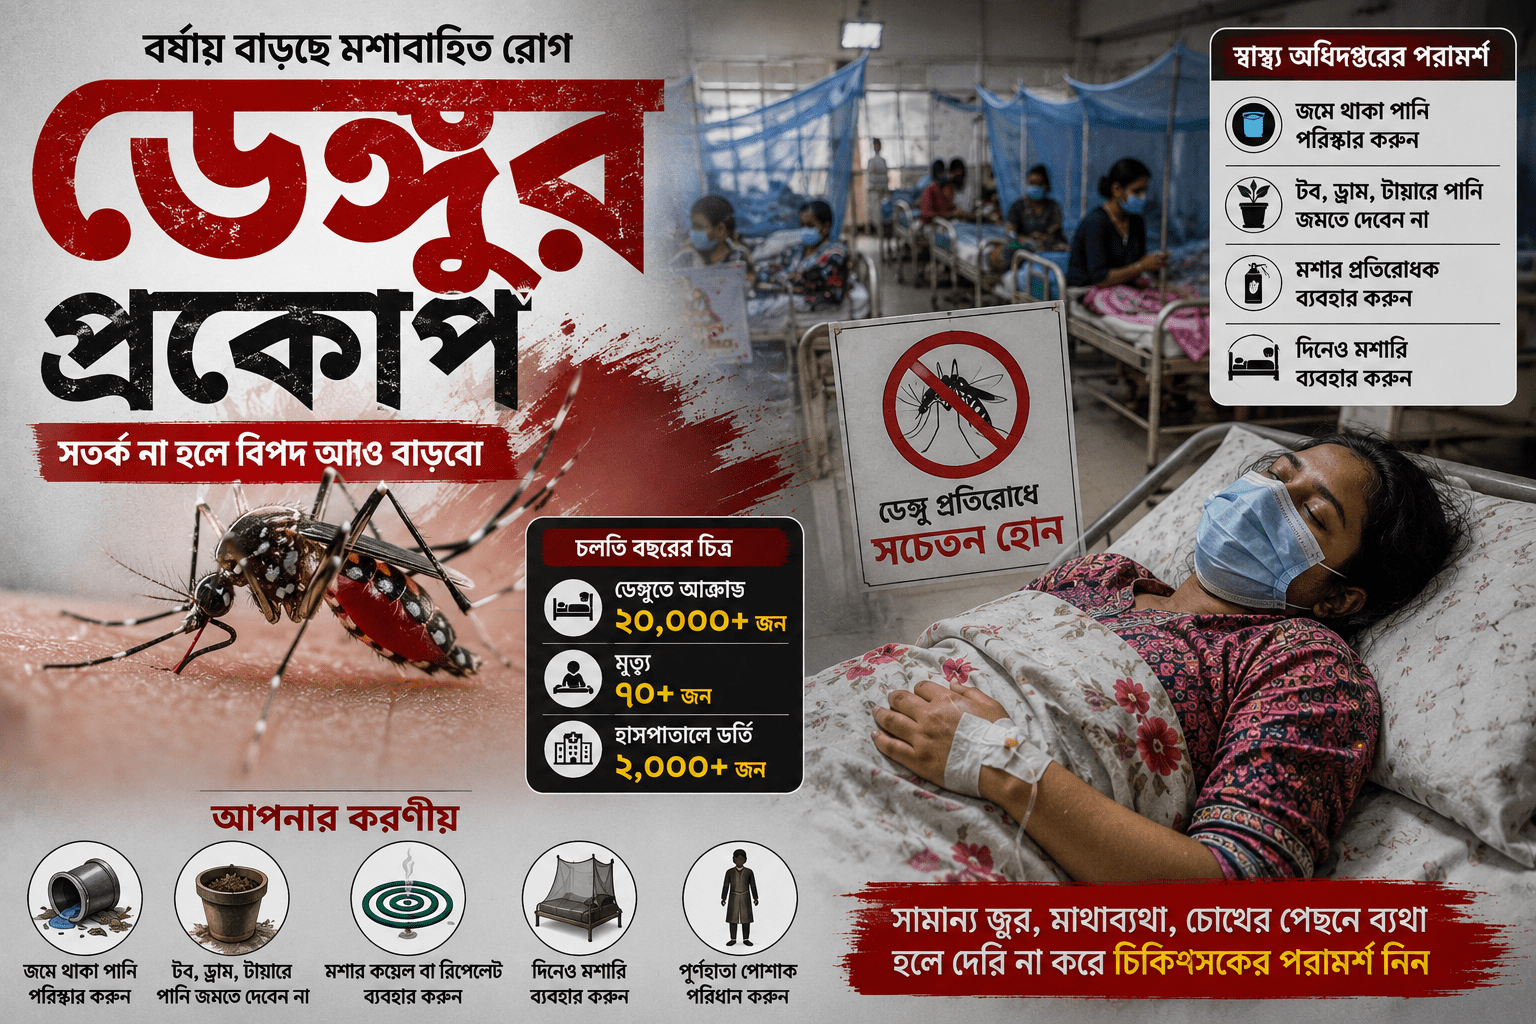

দেশে আবারও বাড়ছে ডেঙ্গুর প্রকোপ। গত ২৪ ঘণ্টায় ডেঙ্গু আক্রান্ত হয়ে পাঁচজনের মৃত্যু হয়েছে। একই সময়ে নতুন করে ১২৪ জন বিস্তারিত..